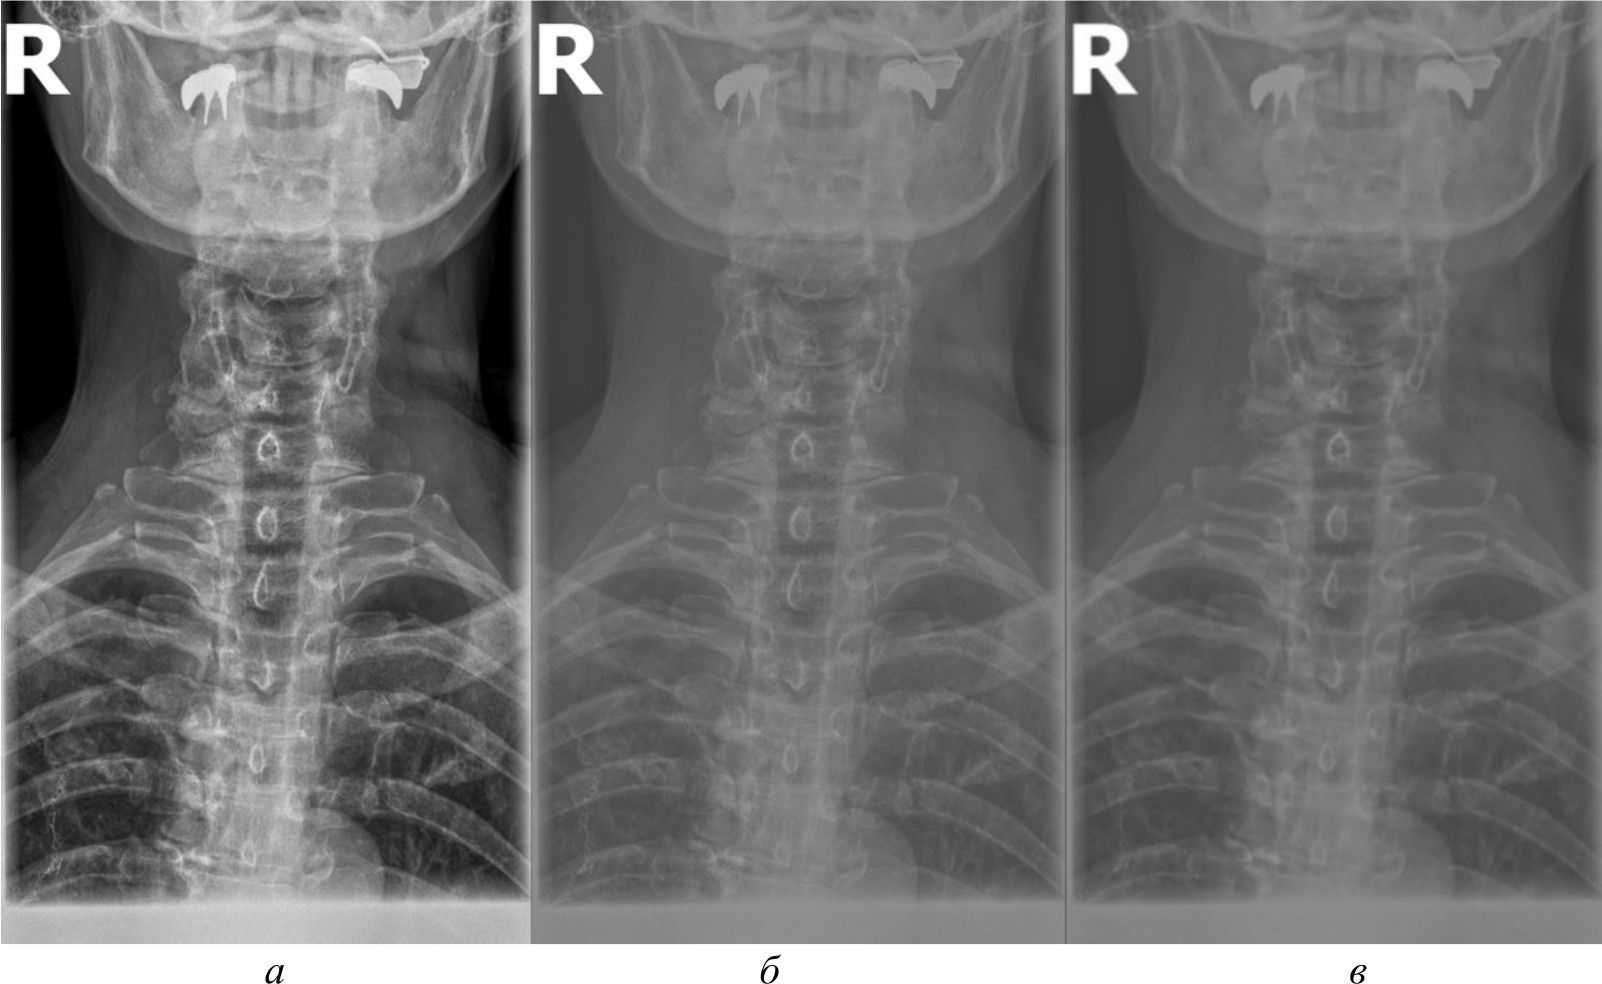

Для создания эталонного набора изображений рентгеновские снимки в формате DICOM были загружены в специализированное программное обеспечение для медицинской визуализации. DICOM является стандартным форматом для медицинских изображений, который позволяет сохранять изображение с высоким качеством и дополнительной информацией об исследовании. Однако для дальнейшей обработки и анализа эти DICOM-файлы конвертируются в более распространенные графические форматы. Специализированное программное обеспечение сохраняет их в формате PNG. На рис. 2, а представлено изображение, полученное в результате работы в специализированном программном обеспечении.

Для сравнительного анализа использовались различные методы и алгоритмы компьютерного зрения. Помимо изображений в формате PNG, конвертированных из исходных DICOM-файлов, применялись и другие подходы, направленные на извлечение более качественных изображений непосредственно из DICOM-данных, среди которых:

- базовое отображение Python. Изображения загружены в Python и отображены при помощи библиотеки Pillow без применения каких-либо дополнительных преобразований. Данный метод представлен на рис. 2, б;

- медианный фильтр. Для сглаживания шумов и артефактов на изображениях к базовому отображению Python применен медианный фильтр из библиотеки OpenCV. Размер окна фильтра был подобран эмпирически. Данный метод обработки представлен на рис. 2, в;

- адаптивная эквализация гистограммы. Для улучшения локального контраста изображений помимо базового отображения Python использована адаптивная эквализация гистограммы из библиотеки OpenCV. Метод адаптивной эквализации представлен на рис. 3, a;

- стандартная эквализация гистограммы. Для сравнения с адаптивной эквализацией помимо базового отображения Python применена стандартная эквализация гистограммы из OpenCV. Данный метод представлен на рис. 3, б;

- гамма-коррекция. Для регулирования яркости и контрастности изображений, а также для сравнения с двумя предыдущими эквализациями использована гамма-коррекция. Значение гамма-параметра подбиралось эмпирически. Гамма-коррекция представлена на рис. 3, в.

Рис. 2. Изображение, полученное при помощи специализированного программного обеспечения (а), метод базового отображения в Python (б), метод базового отображения Python с применением медианного фильтра (в)

Исходя из полученных изображений при использовании различных методов можно сделать следующие выводы:

- базовое отображение DICOM-данных с помощью библиотеки Pillow показало наличие значительного количества шумов и размытых объектов на полученных изображениях, что затрудняет четкое обнаружение анатомических ориентиров;

- применение медианного фильтра для сглаживания артефактов привело к чрезмерному размытию деталей на изображениях, сделав их еще менее пригодными для дальнейшего анализа;

- использование методов эквализации гистограммы продемонстрировало значительное улучшение контрастности и четкости визуализации анатомических структур по сравнению с базовым отображением и медианной фильтрацией;

- гамма-коррекция изображений, в отличие от эквализации, больше повлияла на яркость, нежели на контрастность, поэтому показала себя хуже в контексте задачи выделения ключевых анатомических ориентиров;

- отображение изображений в формате PNG, полученных из исходных DICOM-данных после применения ряда предварительных обработок с помощью специализированного программного обеспечения, продемонстрировало качество визуализации несколько меньшее, чем у методов эквализации, но при этом превосходящее качество других рассматриваемых методов обработки. В итоге комплекс предварительных обработок, необходимых для конвертации DICOM-данных в формат PNG, позволяет достичь качества визуализации, которое хотя и уступает эквализации, но превосходит другие методы.

Рис. 3. Метод адаптивной эквализации гистограммы, метод стандартной эквализации гистограммы, метод гамма-коррекции